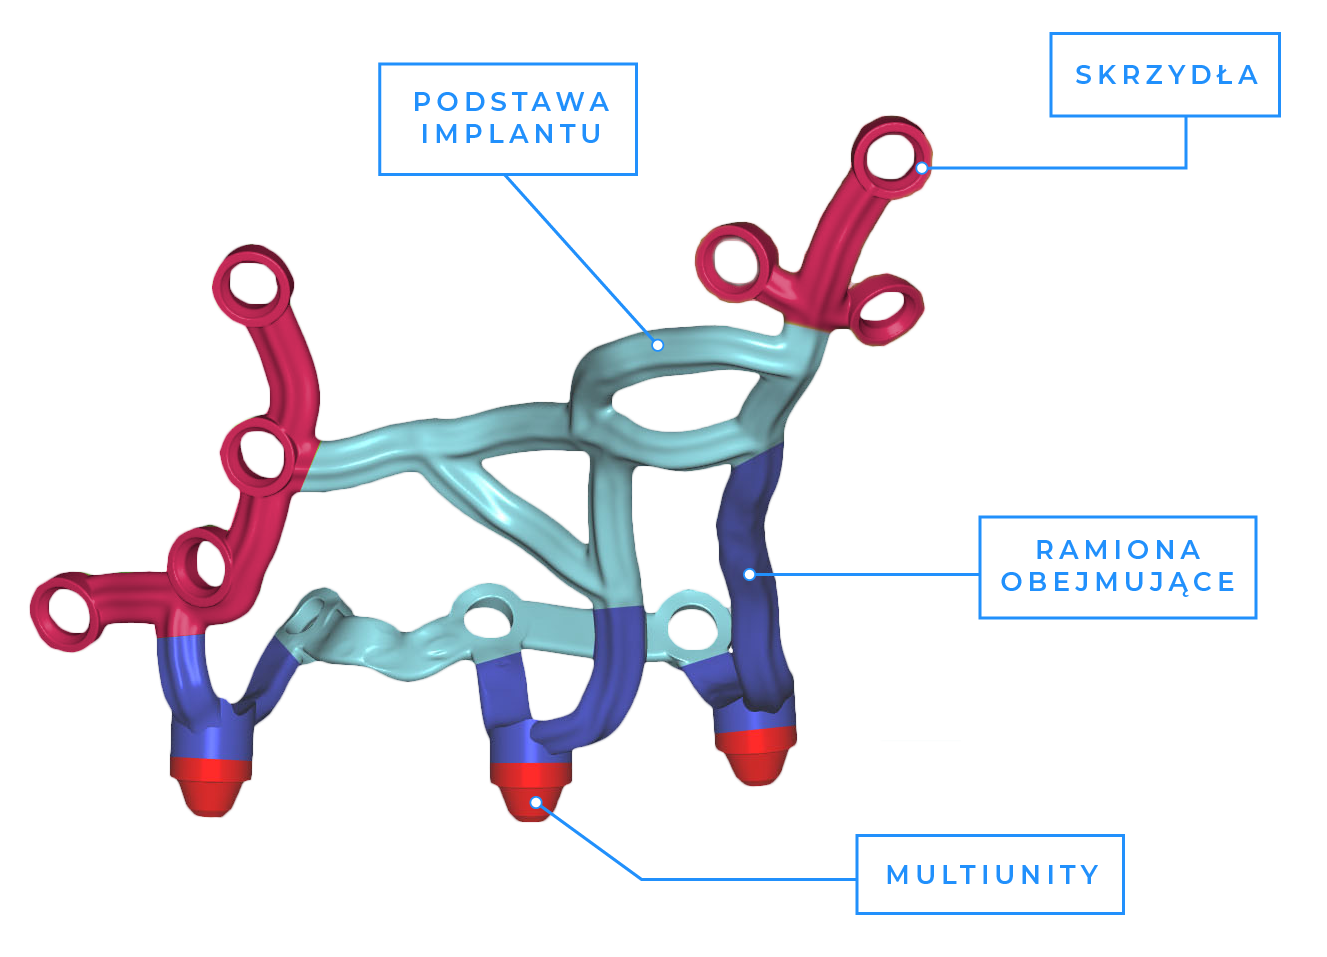

2. Budowa indywidualnych implantów podokostnowych

Jedno z najnowocześniejszych rozwiązań implantologicznych polega na zaprojektowaniu i wytworzeniu siatki okalającej, która zostaje przykręcona do kości.

Na tej konstrukcji zostają zamocowane elementy łączące implant z pracą protetyczną.

Implanty podokostnowe to indywidualne rozwiąznie dla pacjentów ze znacznym lub całkowitym zanikiem tkanki kostnej, u których niemożliwe jest wprowadzenie implantów korzeniowych oraz zastosowanie zabiegów regeneracji kości.

Implanty podokostnowe stanowią spersonalizowaną konstrukcję przestrzenną dedykowaną konkretnemu pacjentowi.